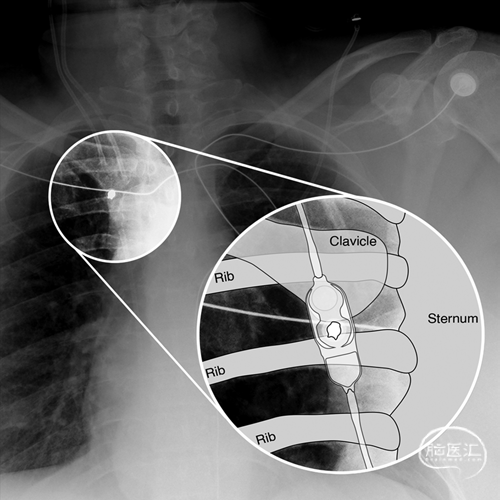

图1展示了病例1的脑室大小变化过程,包括置管后12个月随访影像学表现稳定。图2为分流系列检查中的胸片图像,示意图显示分流阀置于锁骨尾侧的解剖位置。

图2.术后分流系统定位胸片正位像,显示分流阀置于锁骨尾侧。示意图放大并标注了解剖结构,明确分流阀相对于锁骨的位置关系: